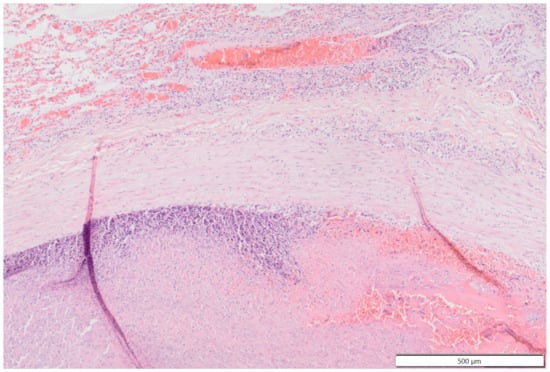

Histologically the right ventricular thrombus was characterized by a massive central zone of amorphous eosinophilic material with occasional scattered cellular debris (fibrin and necrosis) and scattered deposits of hemosiderin and hematoidin pigments. Peripherally, the thrombus consisted of a variably thick layer of connective tissue that was infiltrated by moderate numbers of macrophages, lymphocytes and plasma cells. This inflammatory infiltrate extended into the adjacent myocardium. At the site of electrode insertion, the myocardium was focally replaced by connective tissue and adipose tissue. Multiple coronary vessels had thickened walls that partially occluded the lumens. Multiple pulmonary vessels were obstructed by similar material as described in the right ventricle (thromboemboli) and here this was interspersed with small irregular vascular channels (recanalization) (Figure 9, Figure 10, Figure 11 and Figure 12). Histopathological analysis confirmed marked chronic mural endocarditis and myocarditis with chronic thrombus formation in the right ventricle and pulmonary arteries.

Figure 9.

Photomicrograph overview of the attachment site of the chronic thrombus to the endocardium of the right ventricle. Hematoxylin & Eosin staining, 2× magnification. The insets are shown and described in larger magnification in Figure 10.

Figure 10.

Photomicrographs show the attachment site of the chronic thrombus to the endocardium of the right ventricle. Hematoxylin & Eosin staining, 10× magnification. Marked mononuclear inflammation expands the myocardium (a) and (sub)endocardium at the site of thrombus attachment (b), which is further expanded by vascularized connective tissue confluent with the periphery of the thrombus (organization, (c)). The majority of the thrombus consists of a fibrino-necrotic core with islands of erythrocytes (d).